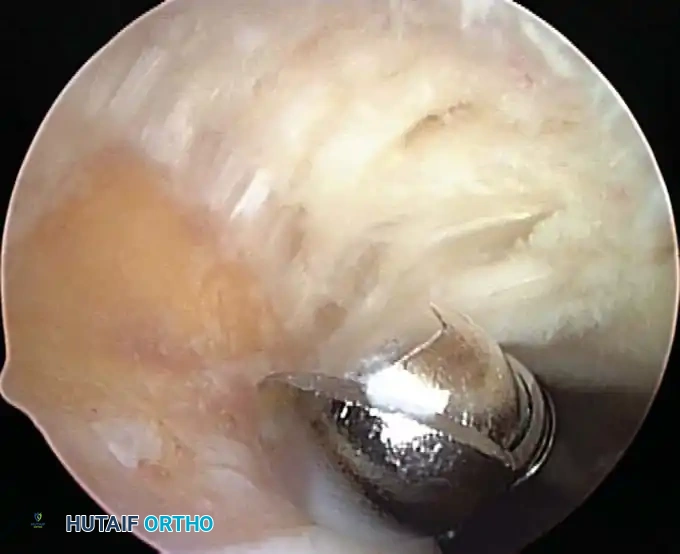

Once diagnostic evaluation is complete and hemostasis is secured, the therapeutic phase commences. Whether performing a SLAP repair, a Bankart stabilization, or a rotator cuff repair, the principles of tissue mobilization, anatomical footprint restoration, and secure biomechanical fixation remain paramount.

Modern arthroscopy relies heavily on suture anchors (biocomposite or all-suture constructs) and advanced arthroscopic knot-tying or knotless techniques. The ability to pass sutures through retracted, fibrotic tissue and secure them under appropriate tension without strangulating the microvascular supply is the hallmark of a master arthroscopist.